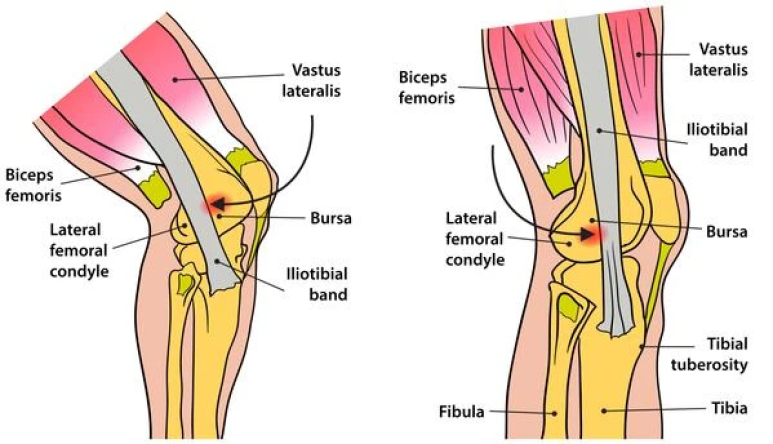

장경인대란?

장골과 경골을 연결하는 인대로

줄여서

장(골) - 경(골) 인대, 장경대라고

부릅니다.

이 장경인대는

대퇴골 뼈 위로

딱 붙어서 지나가기 때문에

오래 뛰거나

등산을 하거나

무리해서 걷게 되면

염증이 생기기

쉽습니다.

장경인대 증후군은

엑스레이에서는

명확하게 보이지 않고

초음파와 MRI 검사에서

진단 되는데요.

출처: Carlos Frederico Arend,Sonography of the iliotibial band: spectrum of findings 위 초음파 이미지에서

빨간 화살표가

장경인대인데요.

딱 붙어있다던

노란색 화살표

대퇴골 외상과와

부딪히면서

염증이 생기게 됩니다.

염증이 생기면

열이 나고

붓게 됩니다.

초기에는

인대 염증으로

녹색 화살표로 표시한

주변 점액낭에

진물이 고입니다.